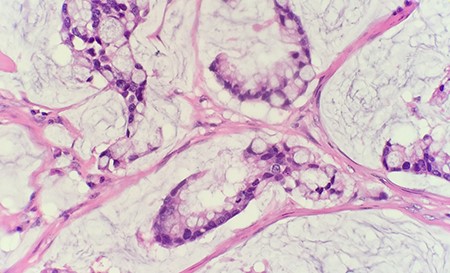

Microscopic examination of the excised mass revealed skin infiltrated by a neoplasm with extensive extracellular mucin pools. Within the mucin pools, there were clusters and strips of malignant intestinal type epithelium. These morphologic features were diagnostic of a moderately differentiated mucinous adenocarcinoma (Fig. 1). The immunohistochemical stains showed that tumor cells were positive for CK7, CK20 and CDX2 while negative for CK5/6 and PAX8, supporting an intestinal phenotype (Fig. 2).

Microscopic examination reveals within the mucin pools are clusters and strips of malignant intestinal type epithelium (HE 40 × ).